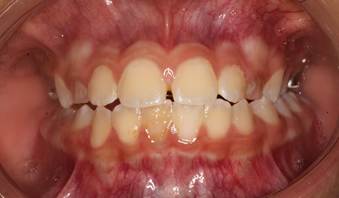

Figura 4. Análisis intraoral

Al examen intraoral se observa una mordida borde a borde de los incisivos antagonistas. La línea media dental inferior está desviada 1mm hacia la derecha. Piezas deciduas con signos clínicos de amelogénesis imperfecta.